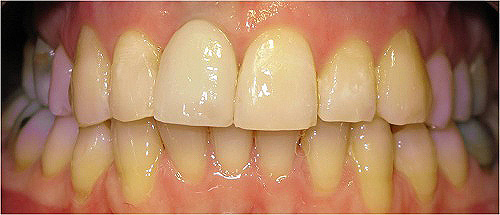

Resultado de colocação de implante dentário na Clínica São Filinto

Caso 1 - Implante imediato após extração do dente fraturado (dente 11) e implante imediato

![]() |